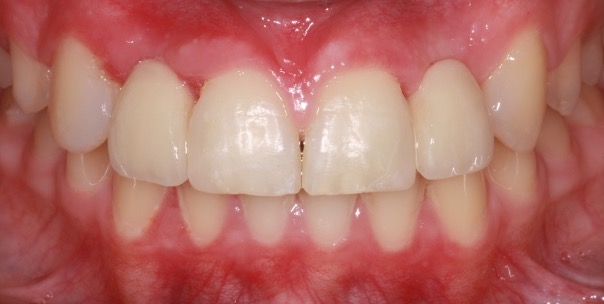

Another case of mild toothwear and discolouration was treated with direct composite bonding.

Composite bonding can also be carried out to close spacing and change the colour of teeth particularly when orthodontic treatment is not desired and tooth whitening has been attempted.